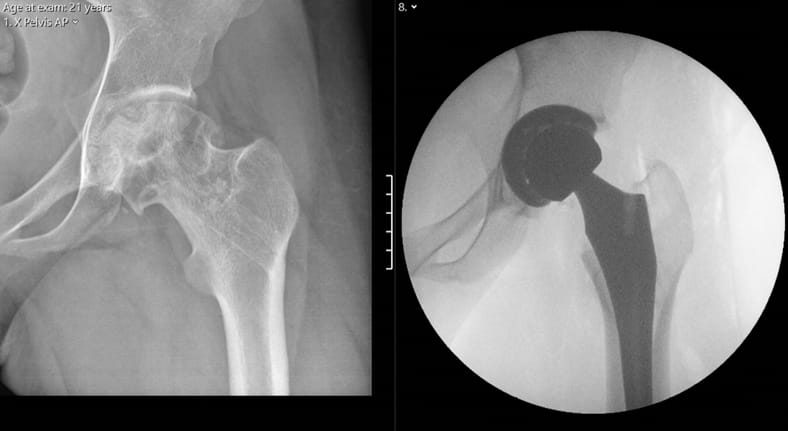

Post-traumatic osteoarthritis of the hip following fracture may result in severe pain and reduced mobility. Total hip replacement is an excellent...